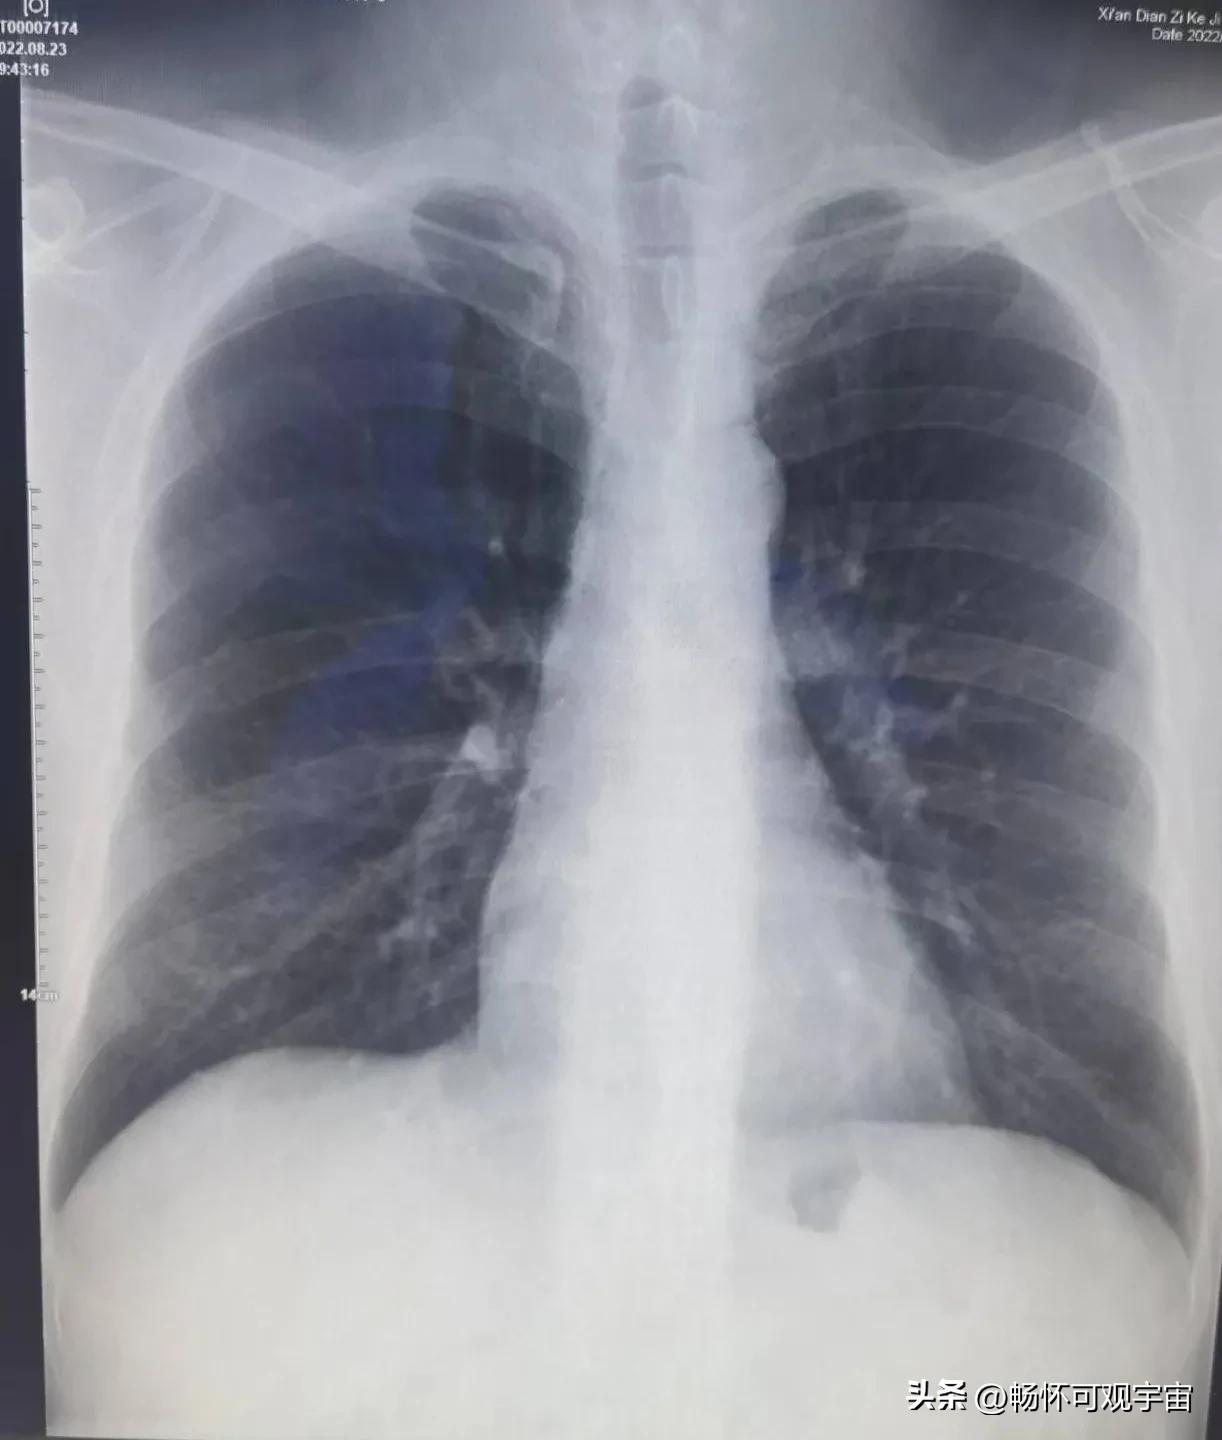

看不懂所以然

X光拍片诊断结果

从X光片上可以看到疼痛的肋骨部位有一道细纹,我问是不是肋骨裂了,医生说不好判断(我觉得是学校医院的设备过于陈旧,拍不清晰)。最后医生诊断是胸壁挫伤,需要静养,多喷喷云南白药。

我给王医师发了信息,他竟然看完我X光片夸我骨密度保养的还不错。